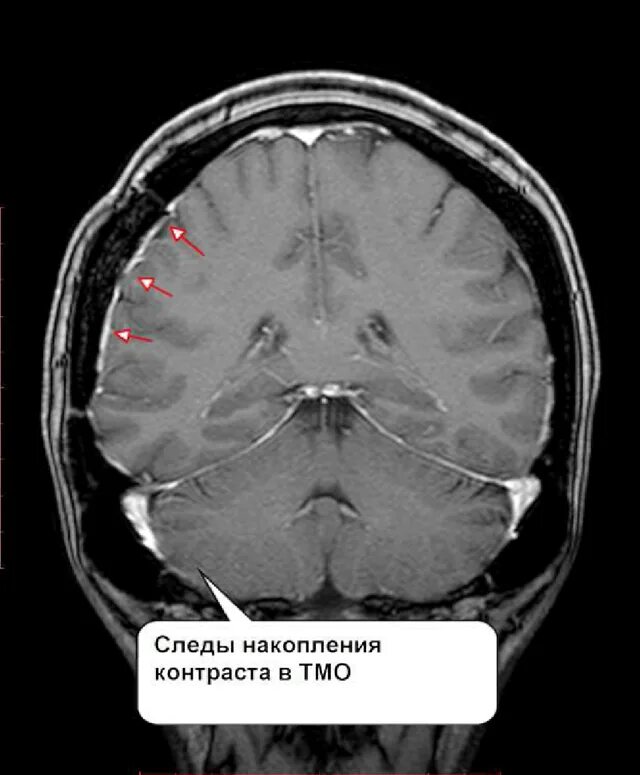

Что покажет мрт головного мозга с контрастом